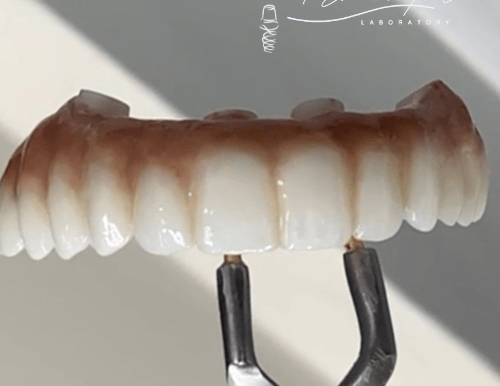

Prótesis dentales con precisión

Soluciones en zirconia, metal porcelana, acrílico y TCS para cada paciente

Creamos prótesis fijas y removibles con materiales como zirconia, metal porcelana, acrílico y TCS.

Prótesis Fijas

Prótesis Fija

Trabajamos con zirconia y metal porcelana para restauraciones duraderas.